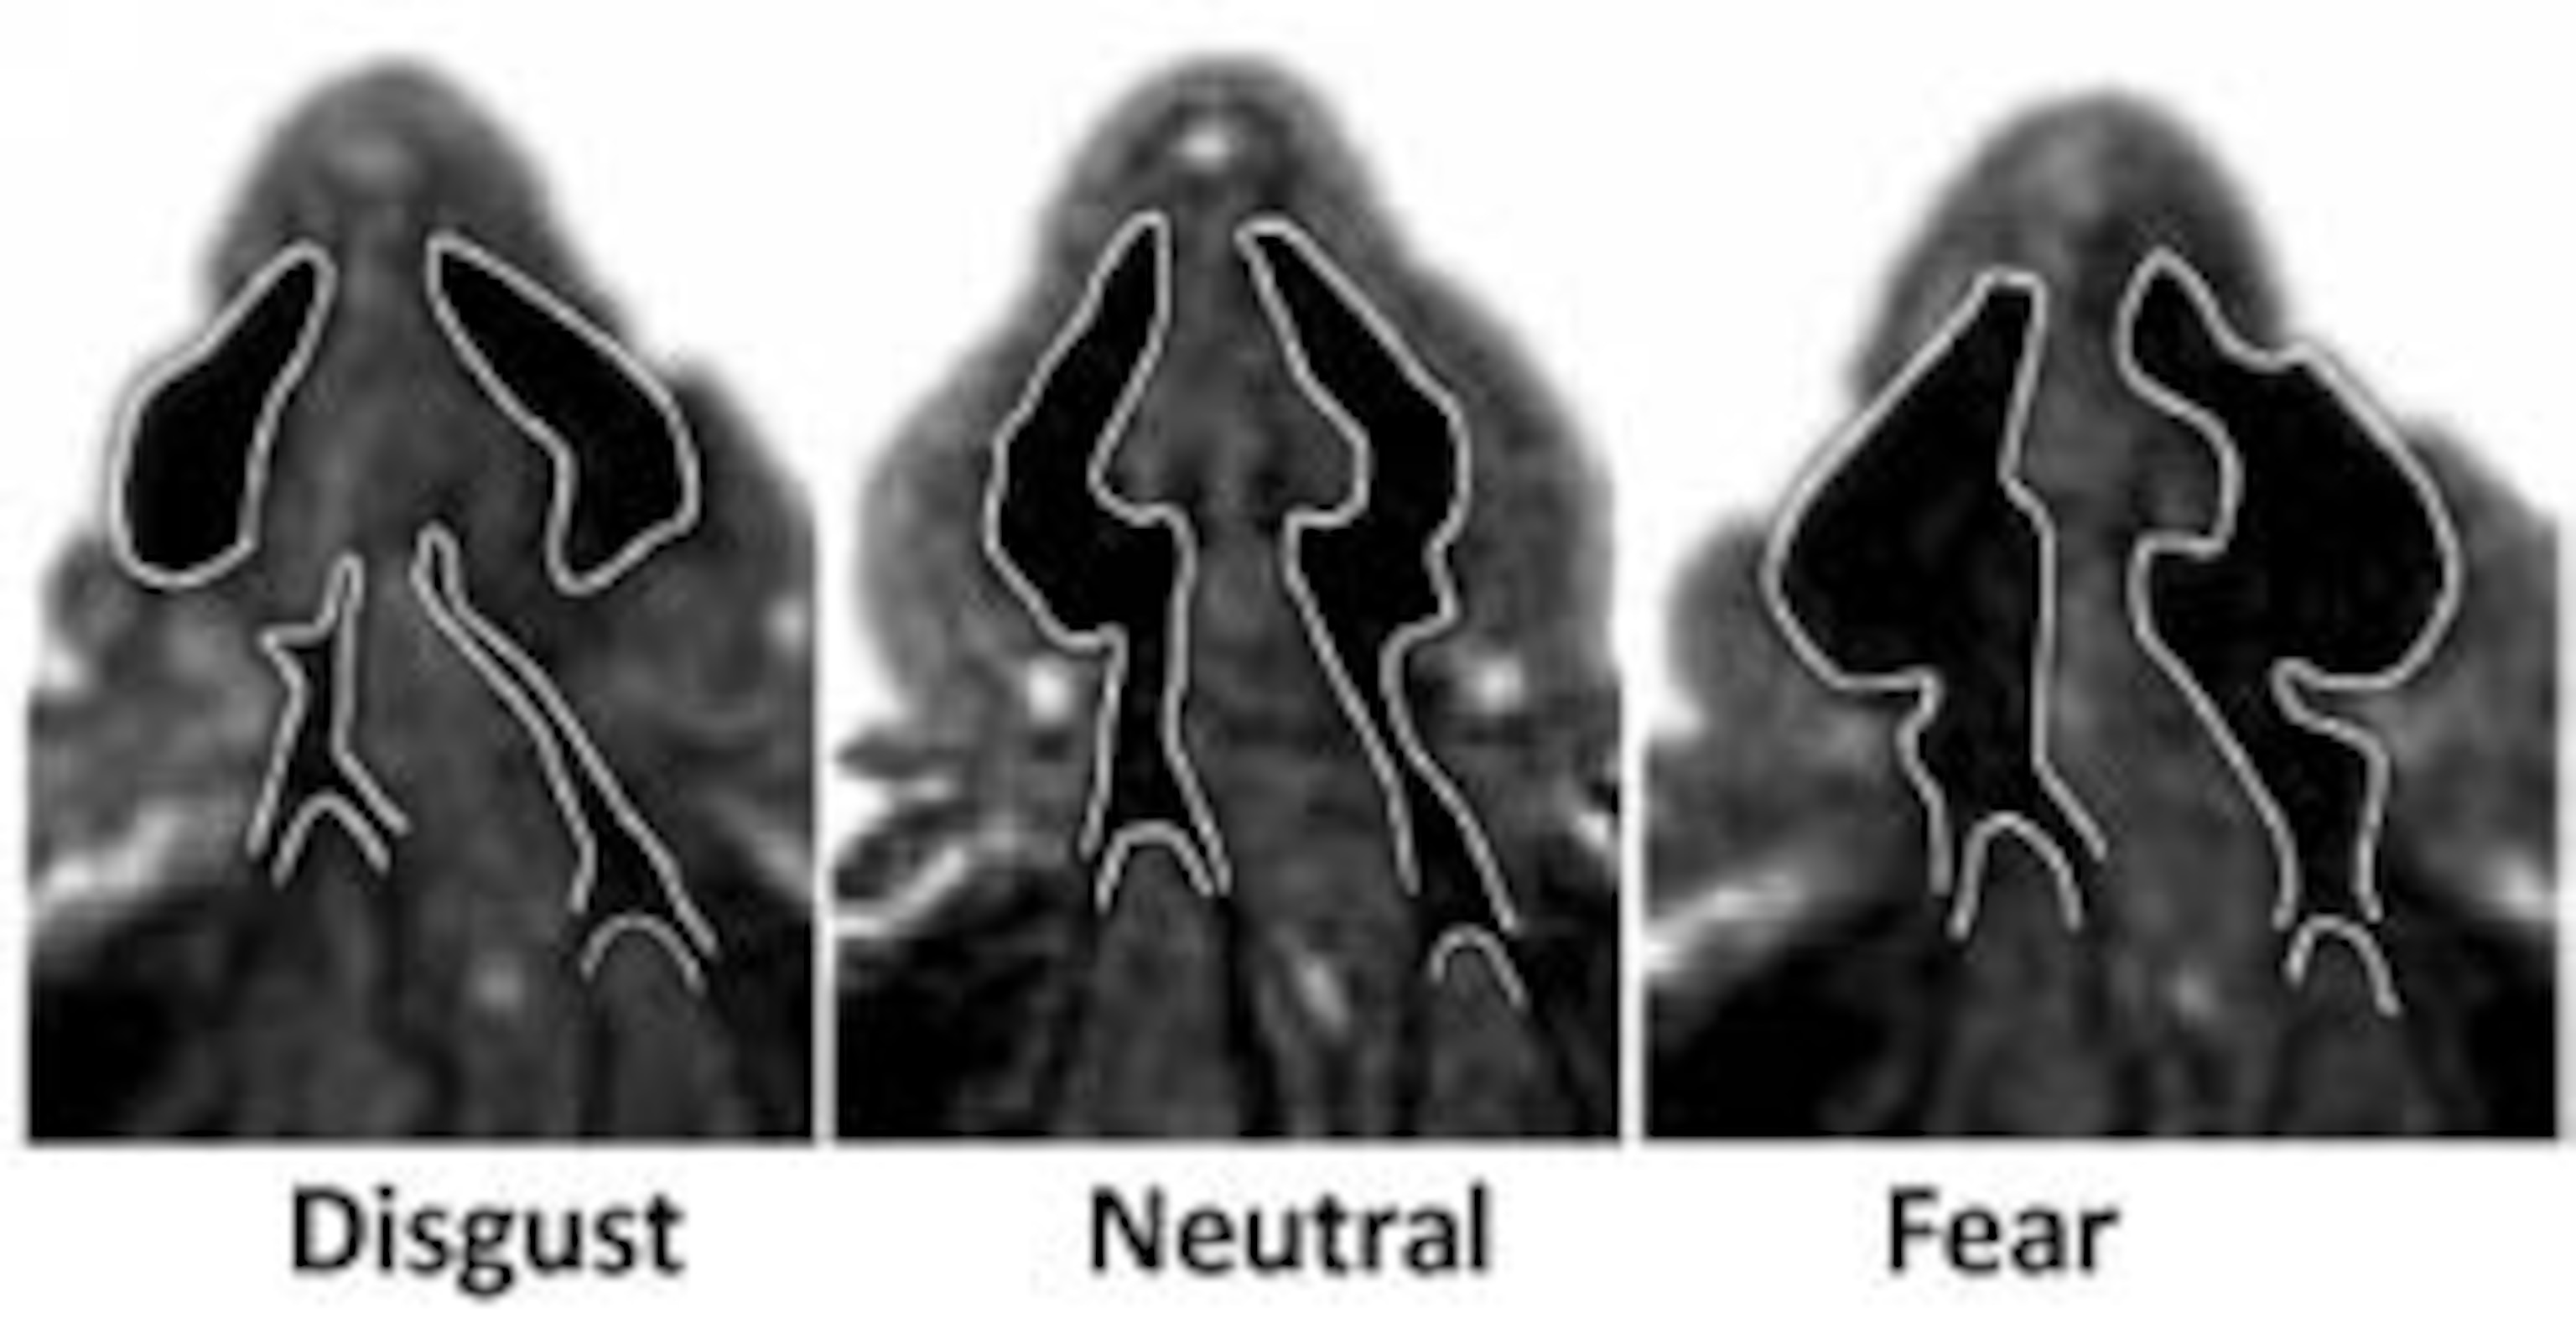

Sight is not the only sense that’s affected – smell gets a boost from fear too. Using airflow meters, Suskind showed that people who look afraid can inhale larger volumes of air than normal, and MRI scans showed that this is due to a widening of their nasal passages. The same passages are sealed off by disgusted expressions, and inhalation volume falls as a result.

Images courtesy of Nature.